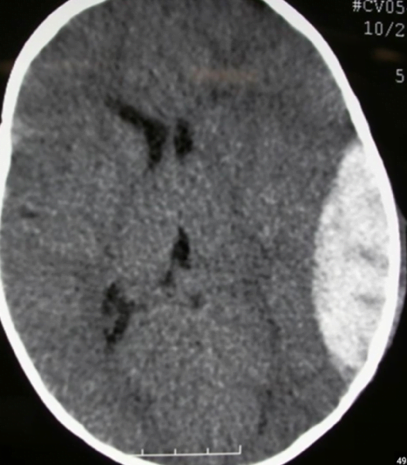

Subdural